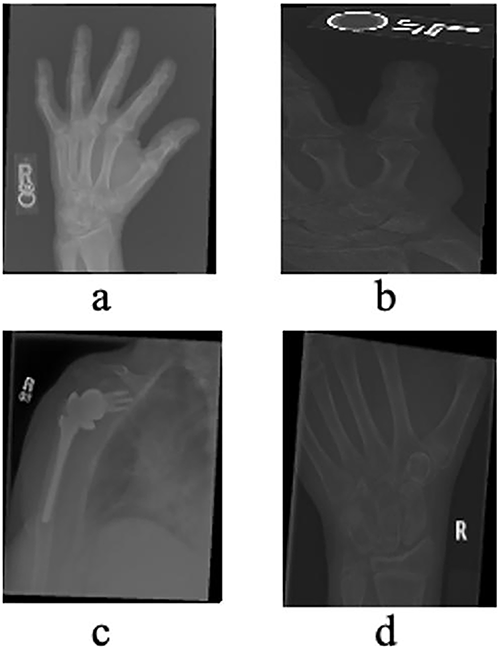

The MURA (Musculoskeletal Radiographs) dataset, originally assembled by the Stanford ML Group, comprises 40,561 X-ray images from 14,863 studies (12,173 patients) across seven upper-extremity regions, including the finger, hand, wrist, forearm, elbow, humerus, and shoulder. All images were extracted from Stanford Hospital’s PACS system, and the authors report that the dataset is Institutional Review Board (IRB) approved, with all radiographs fully de-identified and HIPAA-compliant to ensure patient privacy. The dataset is publicly available for research via its canonical webpage [49]. In this study, we utilized a clinically relevant subset of MURA, specifically radiographs of the hand, finger, shoulder, and wrist (see Table 1 and Fig. 4), as these regions are central to diagnosing fractures and related abnormalities. The problem is formulated as a binary classification task—distinguishing normal from abnormal cases—reflecting realistic clinical workflows where X-rays from multiple healthcare centers are aggregated to support diagnostic decision-making.

Figure 4: X-rays of Hand (a), Finger (b), Shoulder (c) and Wrist (d) taken from the validation dataset